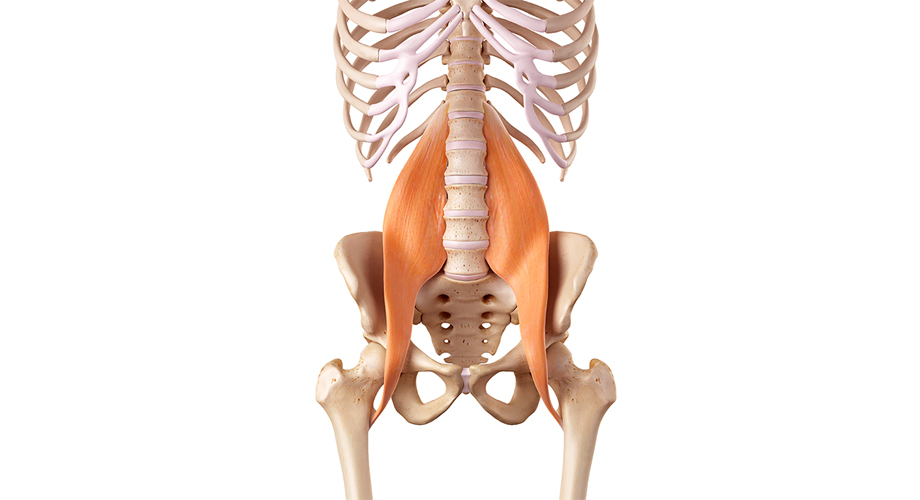

물리치료는 허리디스크로 인한 통증 관리를 위해 효과적인 방법 중 하나입니다. 전문 물리치료사의 지도 아래, 스트레칭과 강화 운동을 통해 근육을 강화하고 유연성을 높일 수 있습니다. 이러한 치료는 회복을 촉진하고, 통증을 줄이는 데 효과적입니다.

운동 요법은 허리디스크 증상이 있는 환자에게 큰 도움이 될 수 있습니다. 전문가의 지도 아래에 적절한 운동을 통해 근력을 키우고, 허리의 안정성을 높일 수 있습니다. 이는 통증을 줄이고 재발을 예방하는 데 기여할 수 있습니다.